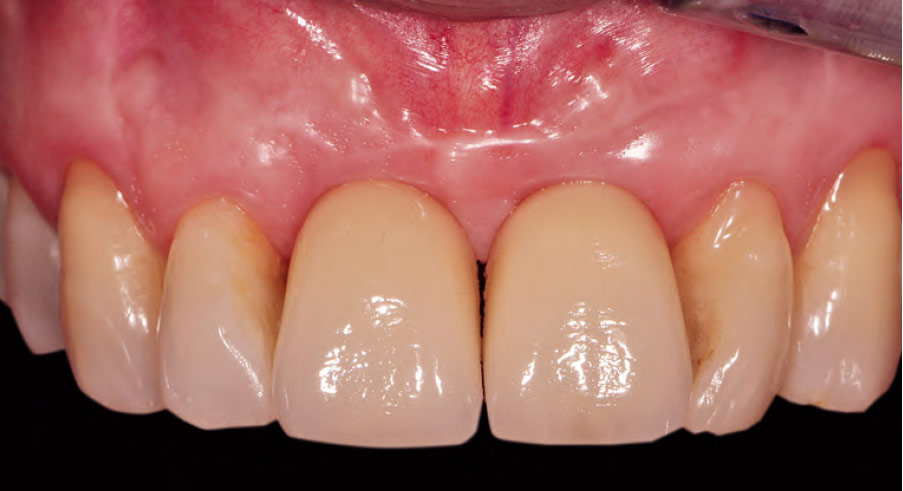

Si, infatti in ciascun capitolo sono presenti numerose immagini cliniche altamente esplicative

allo scopo di enfatizzare l'efficacia didattico-formativa del libro.

Nella gallery sotto alcune foto tratte dai capitoli del libro. Queste foto sono del prof. Eugenio Romeo